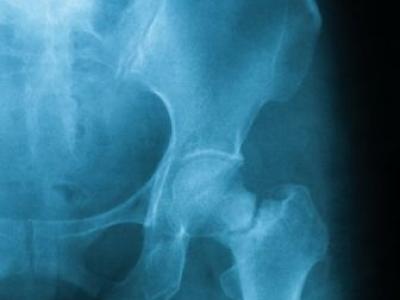

Japan IORRA RA registry shows from 2011 to 2023, despite better Rx & control & less pred, Fractures went up in R

Japan IORRA RA registry shows from 2011 to 2023, despite better Rx & control & less pred, Fractures went up in RA. From 2011 to 2023- DAS resmission 38 to 65%, bDMARD use 14 to 42%, GC use 38 to 22%, OP Rx 32 to 38%; But all FX incr 47 to 53/1000 Pys. https://t.co/cgz0Gkasai https://t.co/D2Uro7mEAT